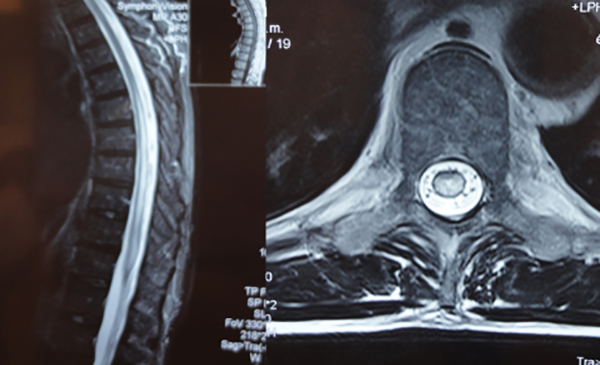

CASO #2. Paciente masculino de 72 años con una historia de 12 meses de parestesias progresivas y ascendentes en ambos miembros inferiores, sin compromiso esfinteriano. Se estudió con RMN (Fig. 9) y una ADM (Fig.10) que muestra una FDAVE en D7 izq. en coincidencia con el origen de la arteria de Adamkiewicz. Fue derivado para microcirugía (Fig. 11). La evolución postoperatoria fue sin déficit neurológico llevando 108 meses libres de enfermedad.

Figura 9: Caso #2. RMN preoperatoria en secuencia T2, a la izquierda se observa en el corte sagital el característico edema centromedular multisegmentario. A la derecha se aprecia, en el corte axial, los múltiples vasos perimedulares y el edema centromedular.